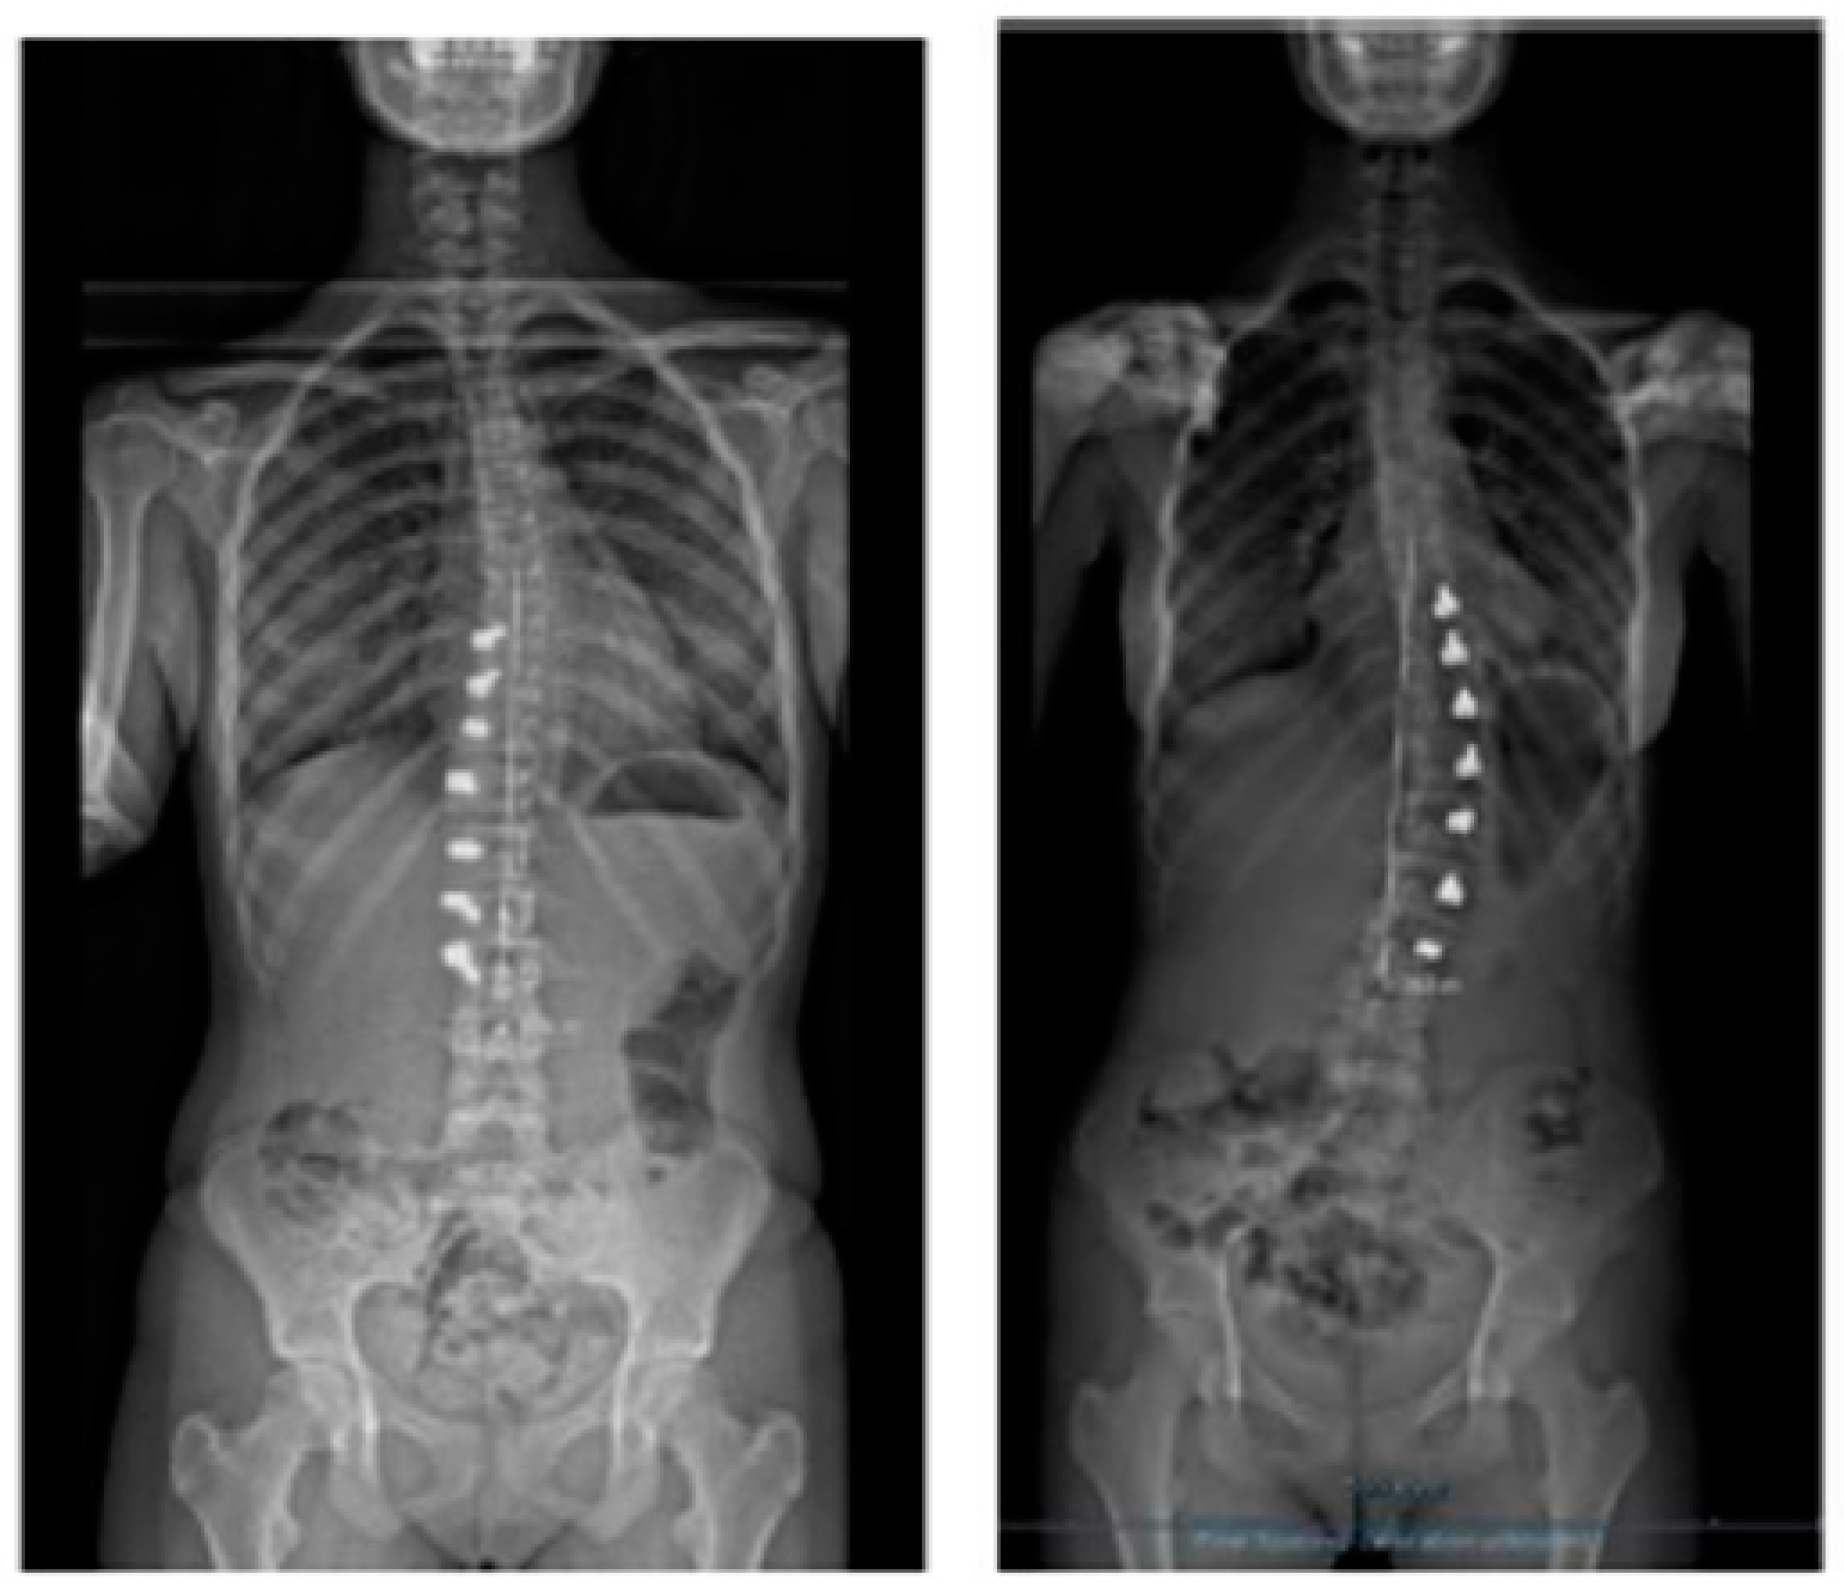

Figure 4.

A 13-year-old adolescent. (A) Pre-op. (B) At 6-month follow up.